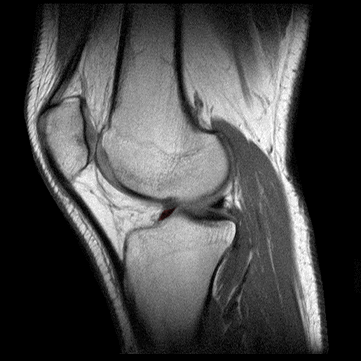

ANATOMIA DE LA RODILLA

El menisco interno es una estructura fibrocartilaginosa en forma de semi-luna unido a la cavidad glenoidea tibial que ayuda a estabilizar el cóndilo femoral lateral y hace de cojín en la cavidad articular. Tiene tres partes: cuerno anterior, cuerpo y cuerno posterior. En comparación con el menisco externo, tiene una forma más parecida a la C (en menisco externo casi una O), más grueso y de una mayor uniformidad.

MENISCO INTERNO: CUERNO ANTERIOR

Origen: El cuerno anterior del menisco interno está unido anteriormente a la protuberancia intercondilar de la tibia.